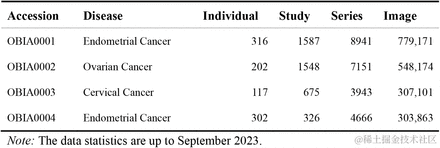

如表 1 所示,这些数据被划进 4 个「Collections」,列示了「Individual」数量、「Study」数量、「Series」数量和「Image」数量。此外,OBIA 还收集了相关临床元数据, 如人口统计学数据、病史、家族史、诊断、病理类型和治疗方法等。

表 1:第 1 批提交给 OBIA 的资料